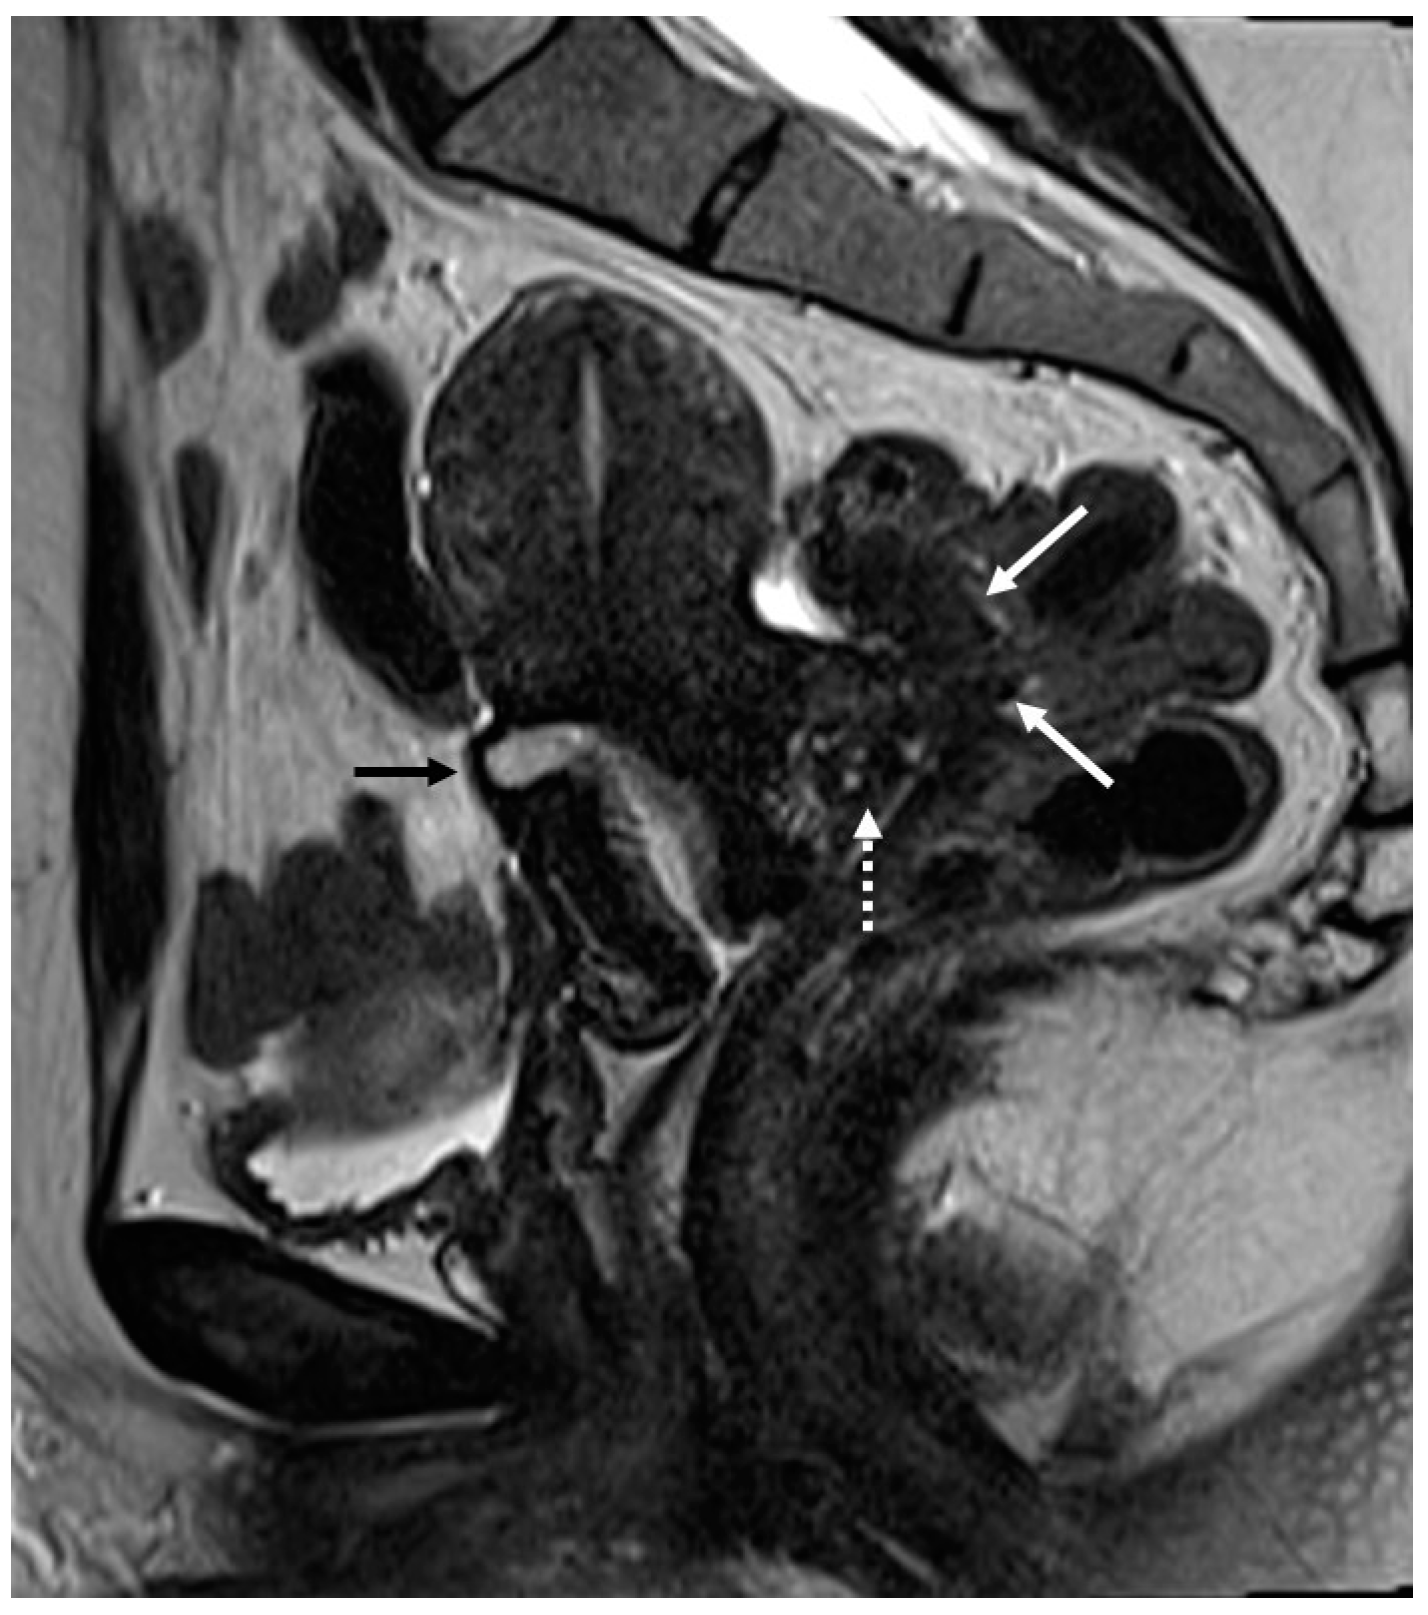

3.2. Deep Infiltrating Endometriosis (DIE)

3.2.4. Rectovaginal Septum

- Rousset, P.; Florin, M.; Bharwani, N.; Touboul, C.; Monroc, M.; Golfier, F.; Nougaret, S.; Thomassin-Naggara, I.; ENDOVALIRM Group. Deep Pelvic Infiltrating Endometriosis: MRI Consensus Lexicon and Compartment-Based Approach from the ENDOVALIRM Group. Diagn. Interv. Imaging 2023, 104, 95–112. [Google Scholar] [CrossRef]